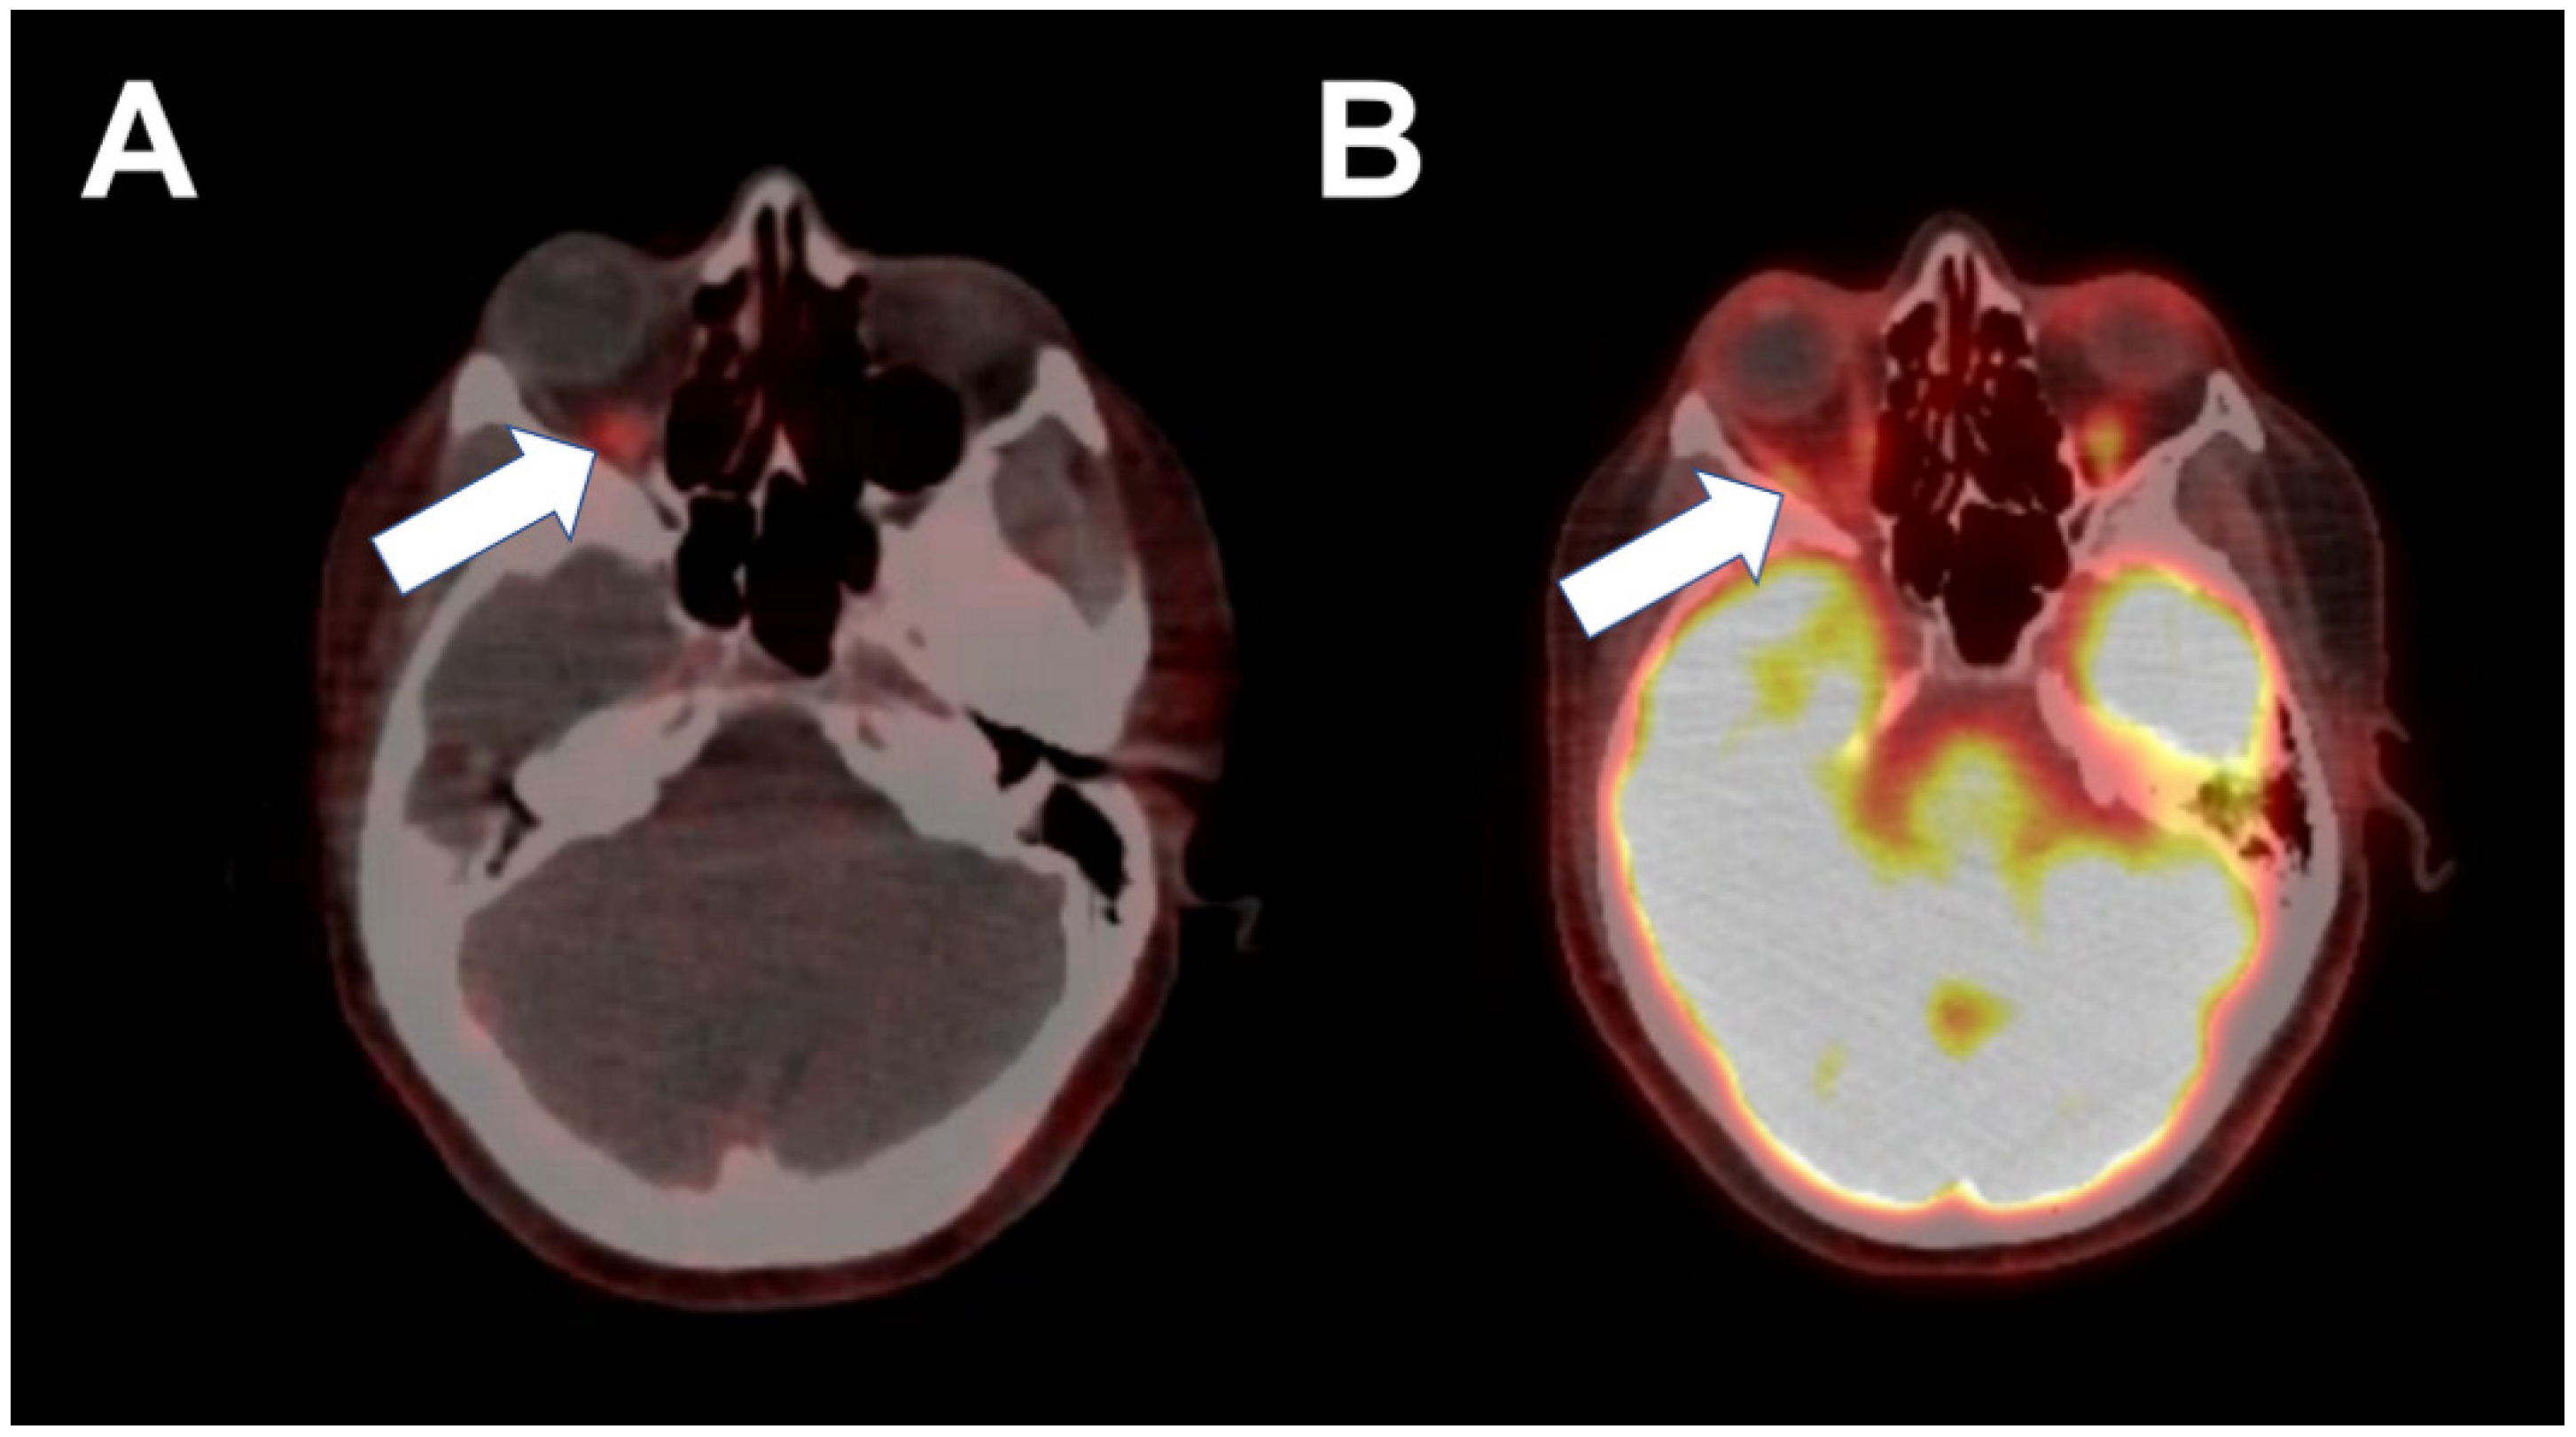

3. Case 2